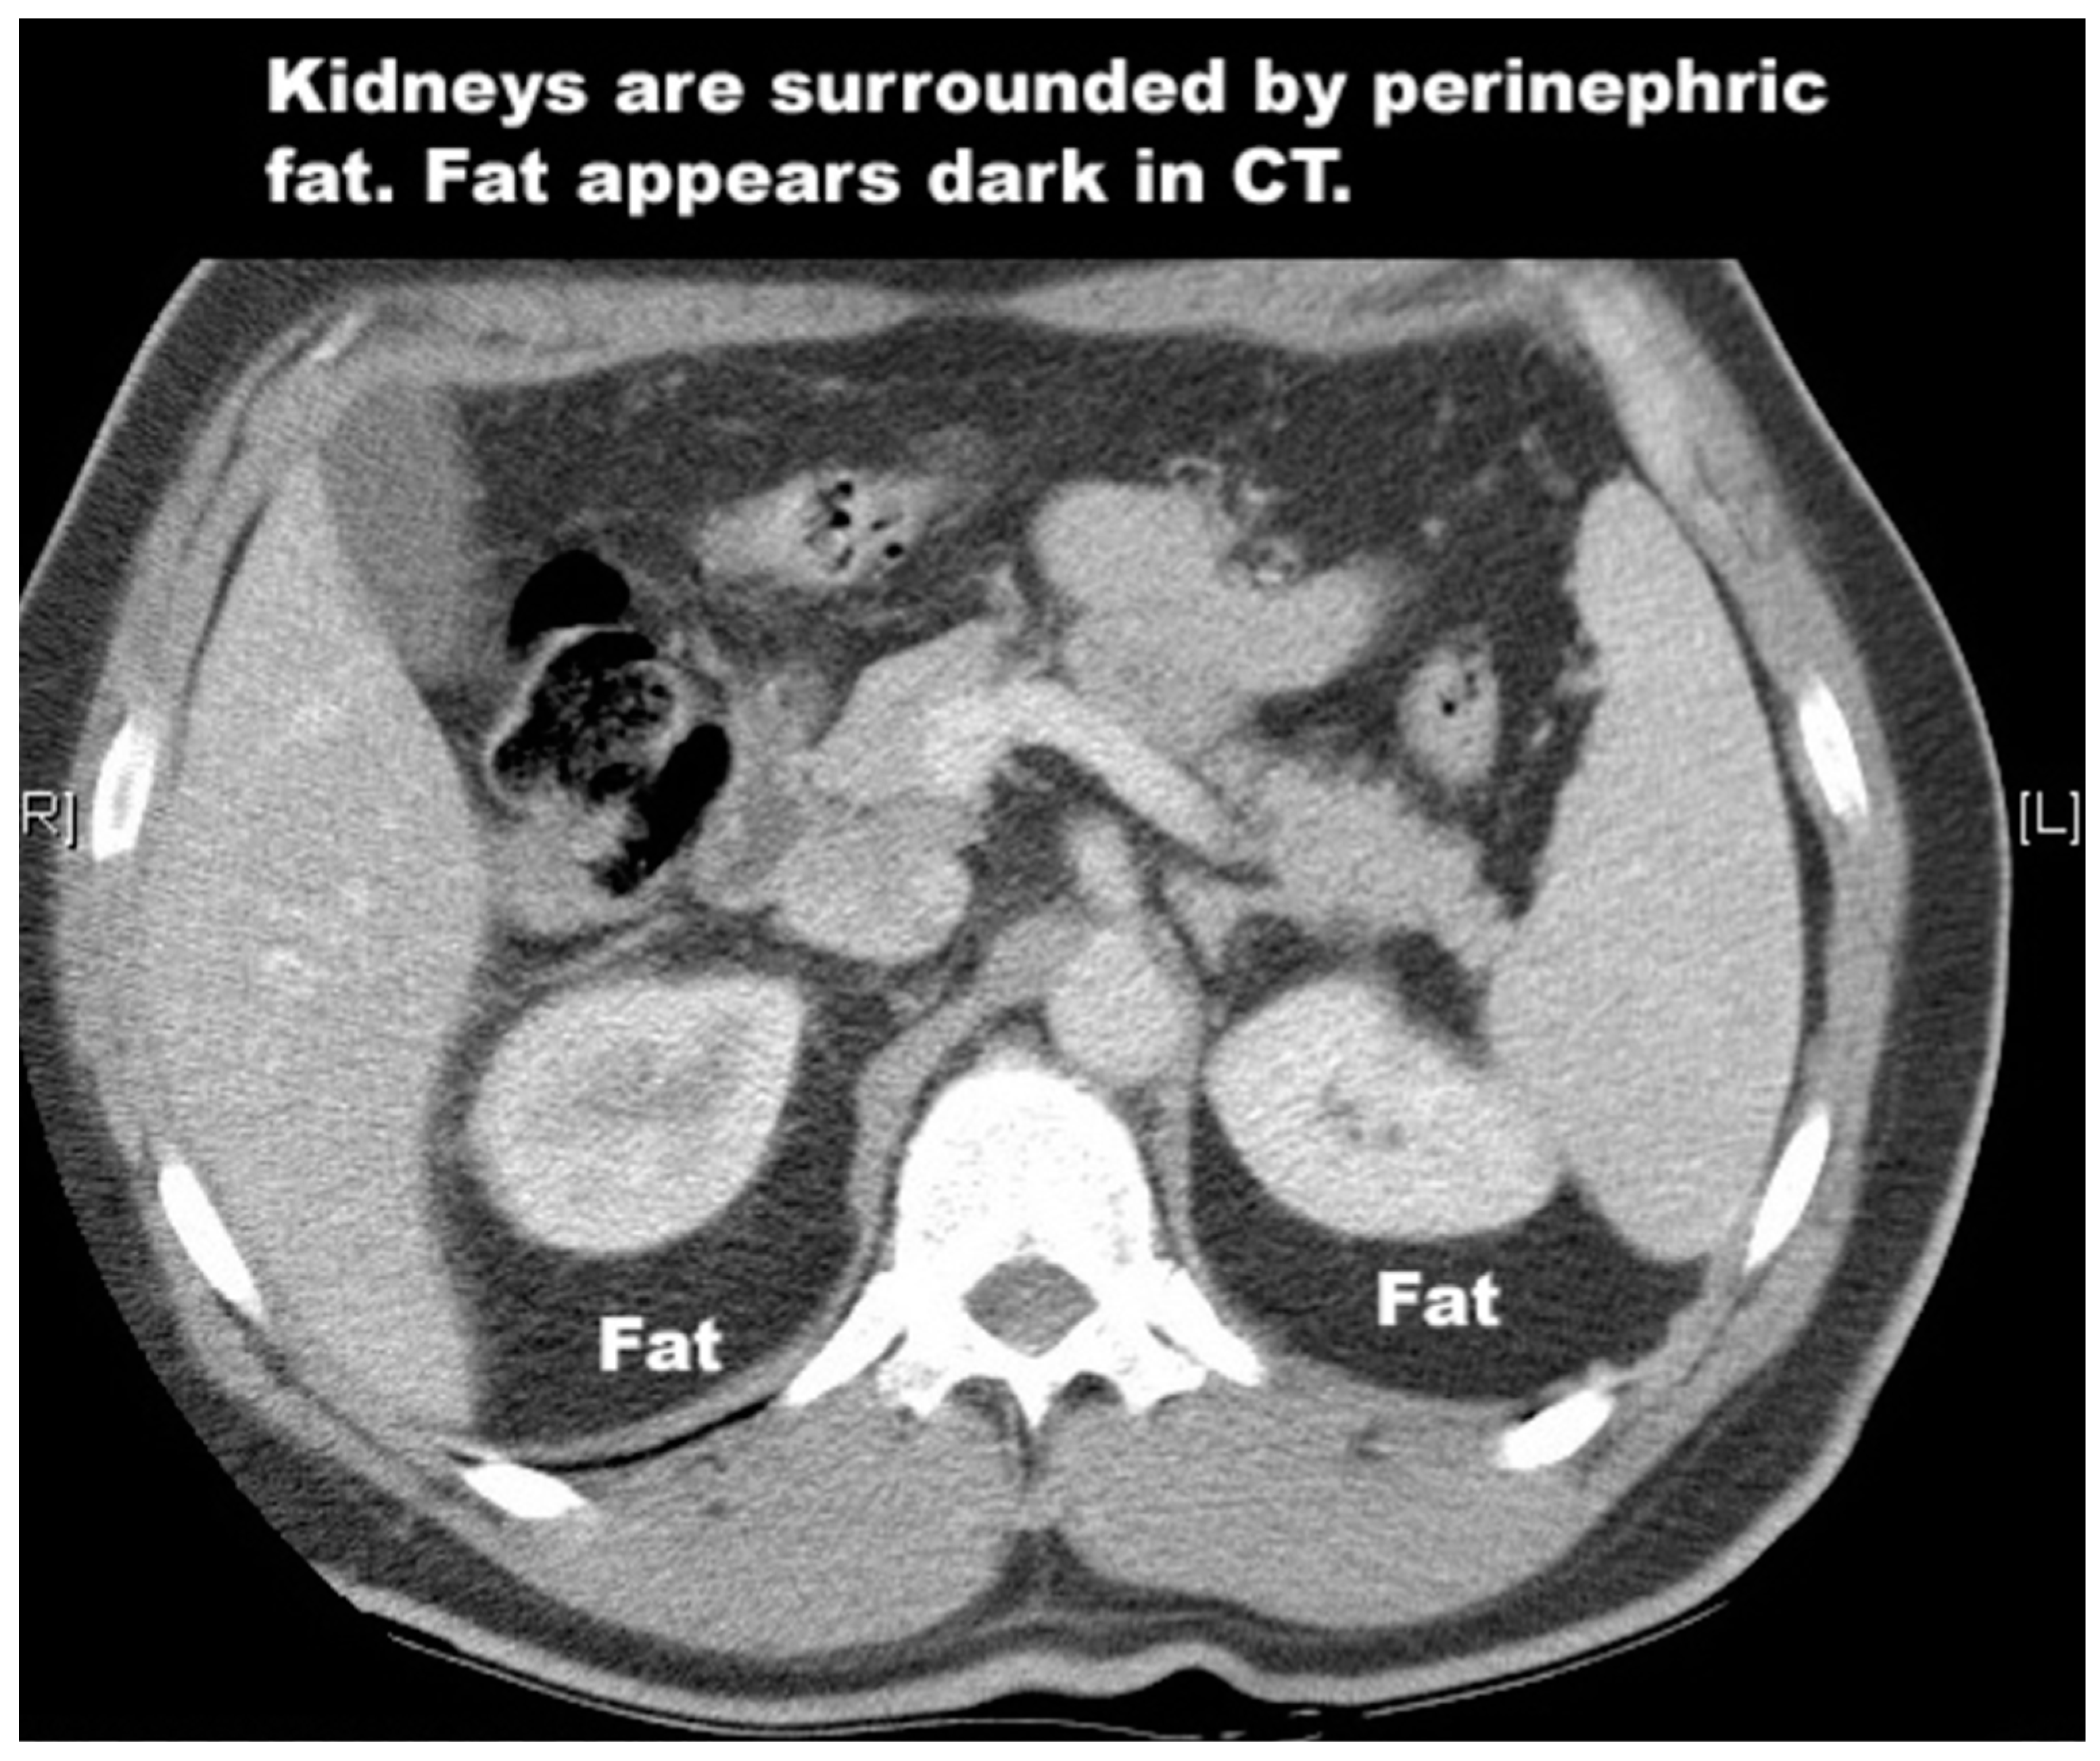

4.1. Kidney